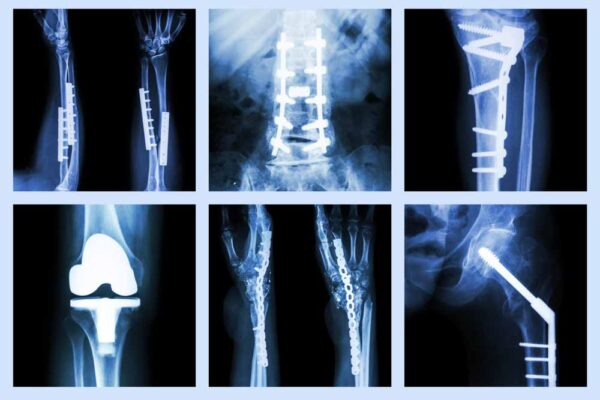

İstanbul’un disiplinli sağlık geleneğini taşıyan kliniğimiz, kas iskelet sistemi hastalıklarında ölçülü dil, net tanı ve kalıcı sonuç çizgisini savunur. Gaziosmanpaşa Ortopedi alanında beklentimiz, hastayı gereksiz işlemlerden uzak tutup bilimsel rehberlere dayalı bir yol haritası oluşturmaktır. Diz, kalça, omuz ve ayak bileği eklemleri başta olmak üzere omurga ağrıları, spor yaralanmaları ve travma sonrası süreçler, planlı bir…